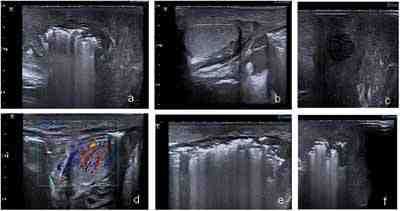

Caso 2: Varón de 48 años con antecedentes de diabetes mellitus tipo II, obesidad, cirrosis enólica con hipertensión portal secundaria, varices esofágicas y rectales. Acude a urgencias por deterioro de estado general e ictericia, secundaria a descompensación de hepatopatía de base. Durante ingreso se solicita ecografía escrotal por tumoración y dolor local, en eco se objetiva tumefacción marcada de tejido celular subcutáneo y partes blandas a nivel escrotal, con testes de aspecto normal, se aprecia gran cantidad de gas que produce artefacto a nivel escrotal (figura 2), sugestivo de absceso escrotal, probable gangrena de Fournier. Tras cirugía se confirma absceso por Enterococo Facium y Escherichia coli, el paciente presentó curso postoperatorio en UCI complicado, ascitis a tensión, insuficiencia hepatorrenal y encefalopatía hepática, entrando en coma irreversible, con resultado final de éxitus.

Figura 2: presencia de gran cantidad de gas en región escrotal que ocasiona artefactos (a,e,f); tumefacción e hipervascularización de partes blandas con testes normales (b,d), áreas de colección y necrosis (c).